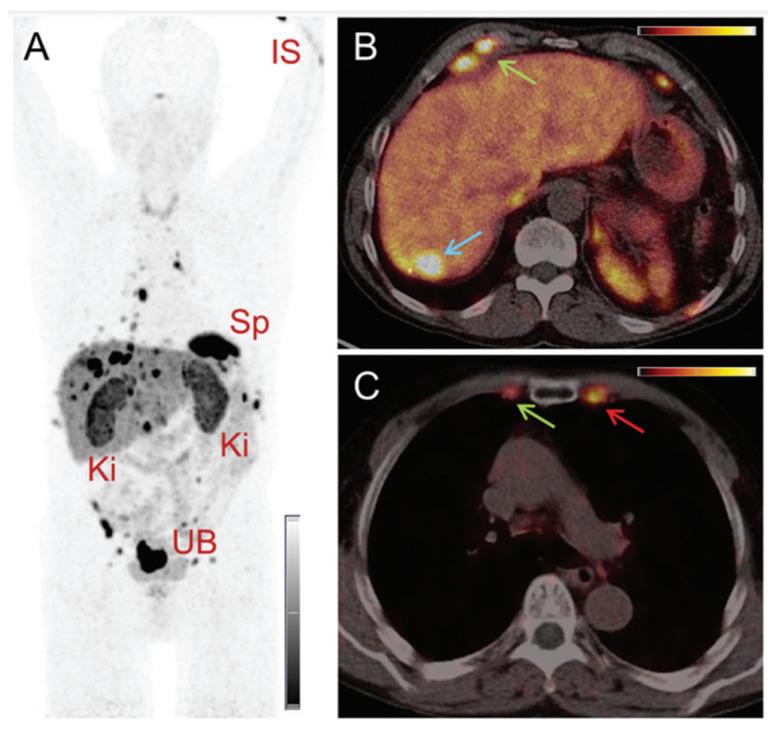

Terbium features four clinically interesting radionuclides for application in nuclear medicine: terbium-149, terbium-152, terbium-155, and terbium-161. Their identical chemical properties enable the synthesis of radiopharmaceuticals with the same pharmacokinetic character, while their distinctive decay characteristics make them valuable for both imaging and therapeutic applications. In particular, terbium-152 and terbium-155 are useful candidates for positron emission tomography (PET) and single photon emission computed tomography (SPECT) imaging, respectively; whereas terbium-149 and terbium-161 find application in α- and β-/Auger electron therapy, respectively. This unique characteristic makes the terbium family ideal for the "matched-pair" principle of theranostics. In this review, the advantages and challenges of terbium-based radiopharmaceuticals are discussed, covering the entire chain from radionuclide production to bedside administration. It elaborates on the fundamental properties of terbium, the production routes of the four interesting radionuclides and gives an overview of the available bifunctional chelators. Finally, we discuss the preclinical and clinical studies as well as the prospects of this promising development in nuclear medicine.